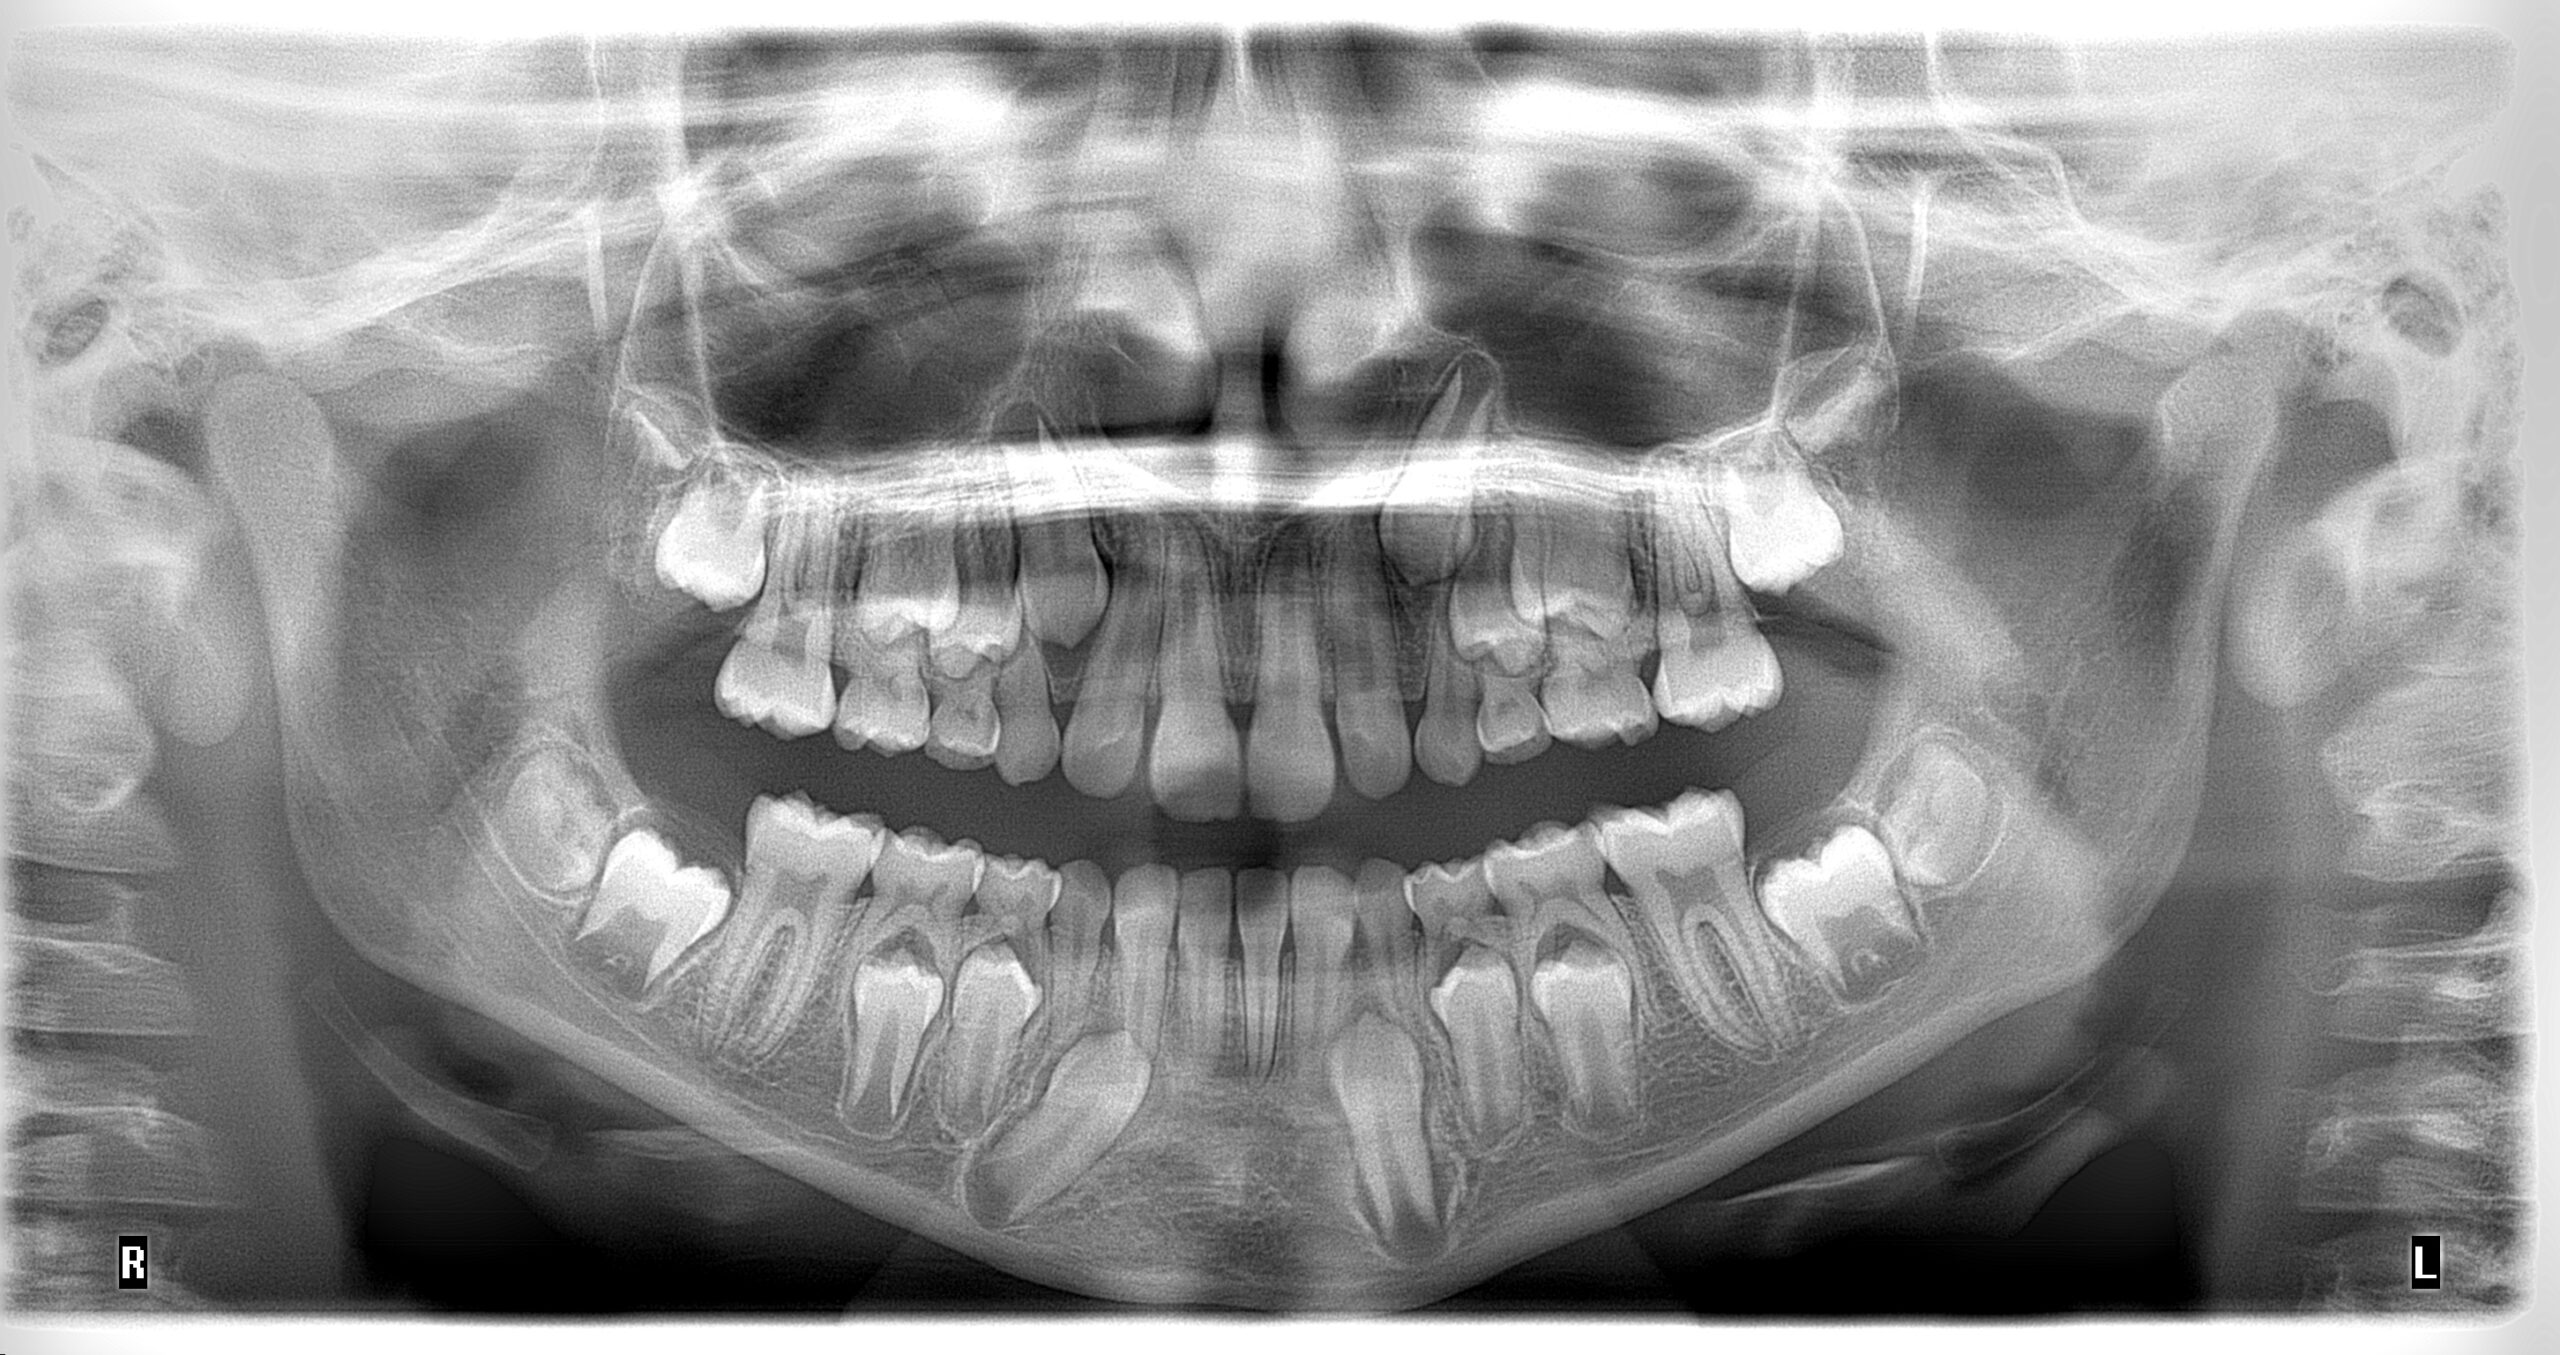

Radiografía panorámica dental en Medellín: La panorámica dental en Medellín es utilizada para tener una visión general del paciente ya que es posible evaluar en conjunto los dientes, el hueso alveolar, los maxilares y las estructuras anatómicas adyacentes, dando una visión detallada de la salud general del paciente

La radiografía panorámica ofrece una vista general del paciente, permitiendo evaluar dientes, hueso alveolar, maxilares y estructuras adyacentes para un diagnóstico integral.